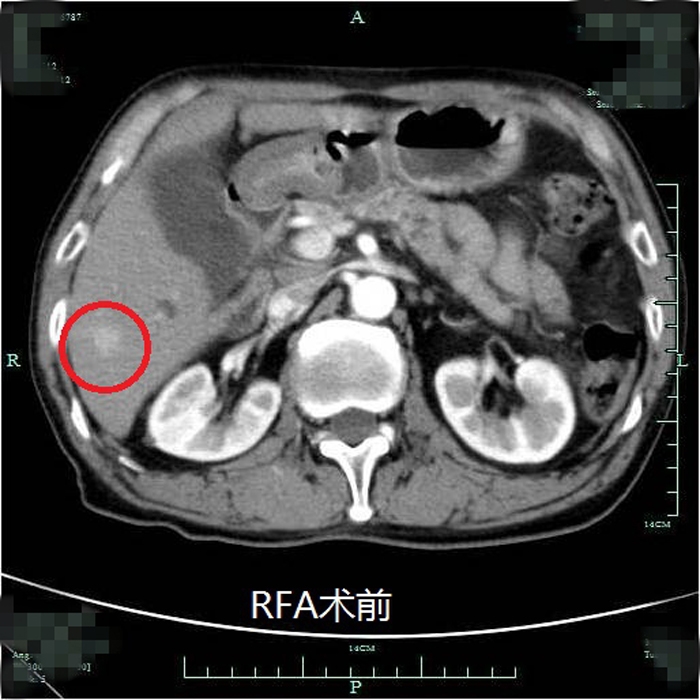

患者術(shù)前尾狀葉腫塊CT顯影

??? 一周前,73歲的毛大爺不幸被查出患上了“癌中之王”-肝癌。這一消息令全家人的心情異常沉重,更糟糕的是約2cm大小的腫瘤長(zhǎng)在肝臟的尾狀葉。

?? 手術(shù)切除是尾狀葉腫瘤的主要治療方式。但由于其位置特殊,手術(shù)難度高,創(chuàng)傷大,風(fēng)險(xiǎn)極高。困擾他們一家的問(wèn)題還不止這些,毛大爺原有肝硬化病史和肺癌手術(shù)史,高昂的手術(shù)費(fèi)用和較長(zhǎng)的住院時(shí)間也成了加重家庭負(fù)擔(dān)的現(xiàn)實(shí)問(wèn)題。有沒(méi)有一種治療效果與手術(shù)相近,而創(chuàng)傷更小、住院時(shí)間更短的治療方法呢?肝膽外科的醫(yī)生團(tuán)隊(duì)討論后決定采用射頻消融術(shù)來(lái)治療毛大爺?shù)奈矤钊~腫瘤。